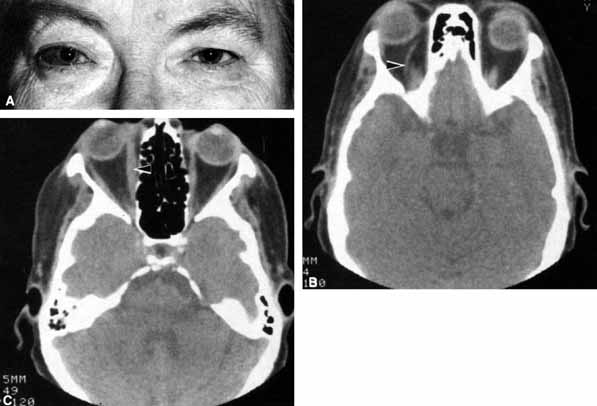

Fig. 19 A. A patient underwent endoscopic exploration of the right ethmoid and maxillary sinus for persistent epistaxis. Postoperatively the patient demonstrates right proptosis, restricted extraocular movements of the right eye, and a dilated right pupil. Instillation of 0.1% pilocarpine resulted in miosis on the right and no change on the left. Computed tomography (CT) shows a vessel clip lateral to the optic nerve (arrow), near the position of the ciliary ganglion. B. Coronal CT scan showing the clip lateral to the optic nerve (arrow).

Damage to parasympathetic fibers proximal to the ciliary ganglion also results in a dilated pupil but without the susceptibility to 0.1% pilocarpine. Trauma, surgery, inflammation, and intracranial aneurysms may produce a dilated pupil. Damage to the parasympathetics proximal to the ciliary ganglion is usually associated with ptosis and third cranial nerve ophthalmoplegia.